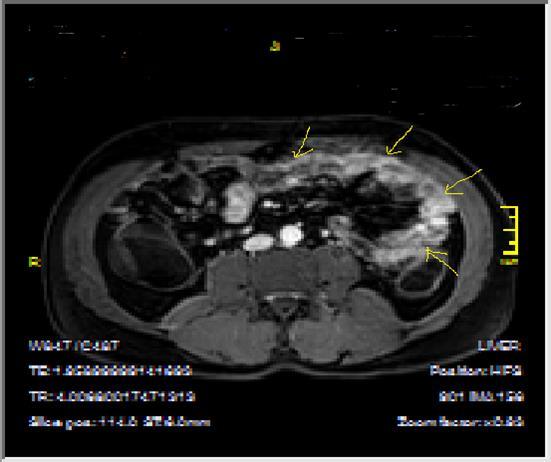

Figure 2a.Concentric luminal narrowing, mural and transmural involvement of terminal ileum due to Crohn’s disease in T2W coronal sequence after OCA application.

Figure 2b.Curvi-lineer, diffuse peripheral enhancing bowel wall in the terminal ileum on axial T1W post-contrast image.